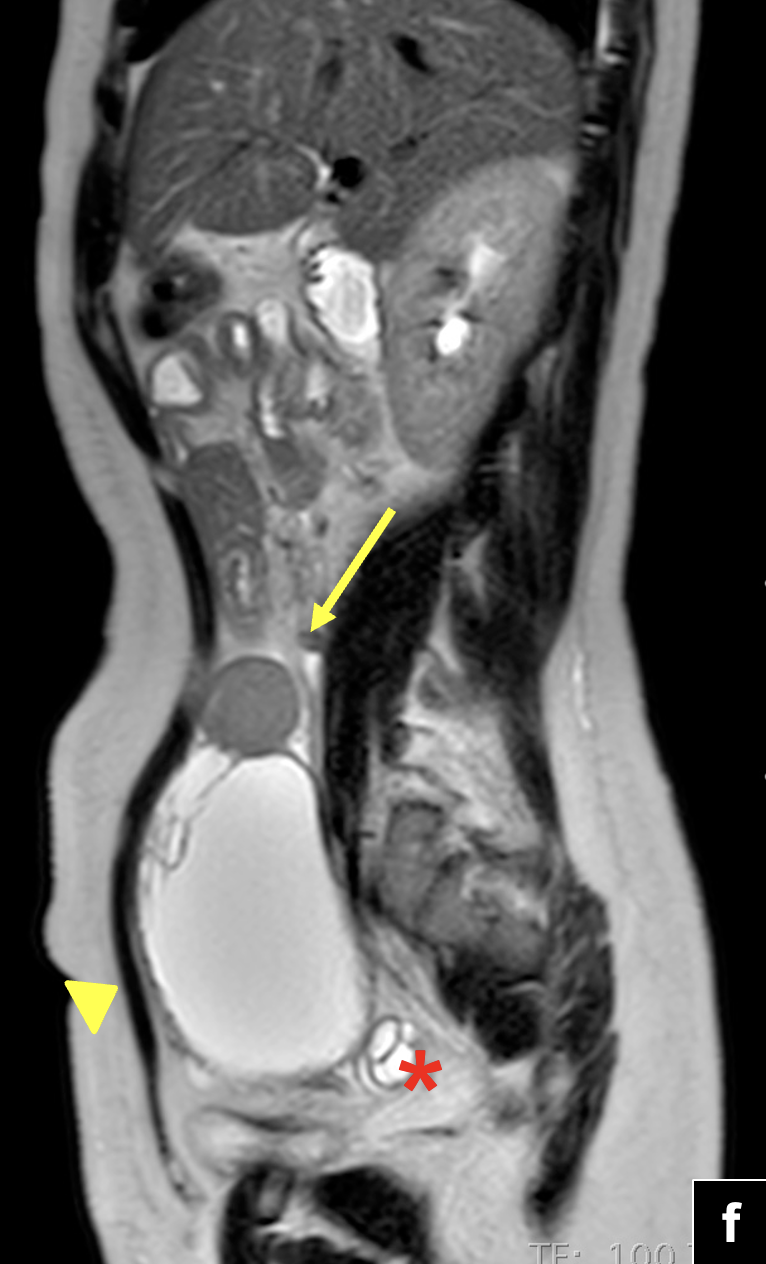

RM de abdomen y pelvis: (f) Secuencias T2 sagital. Se observa tumor solido de íleon distal (flecha) con componente quístico tabicado en hipogastrio (cabeza de flecha). Se visualiza ovario derecho de morfología conservada (asterisco). (g) Secuencia T1 FSE con Gadolinio en plano coronal. Masa quística hipogástrica con tabiques e imagen nodular periférica que realza con el uso de contraste (flecha). Efecto de masa intrabdominal visualizado por el desplazamiento hacia inferior de la pared vesical.Secuencias de pelvis axial en difusión (h,j) y mapa ADC (i,k), que demuestra restricción a la difusión de protones del componente solido del tumor de íleon en estudio y del componente sólido periférico de la masa quística hipogástrica (flecha y cabeza de flecha).